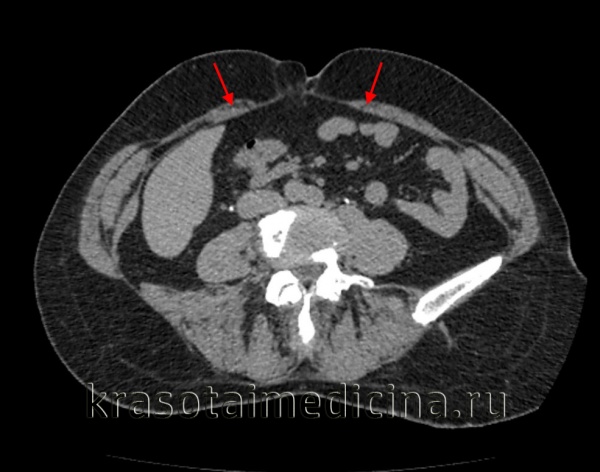

КТ ОБП. Расхождение мышц прямой кишки (красные стрелки) у пожилой женщины.

При стандартных лабораторных исследованиях (клинический анализ крови, мочи, копрограмма) при простом расхождении мышц прямой кишки отклонений от нормы не обнаружено. Для полной оценки состояния внутренних органов, пациентам с осложнениями заболевания могут быть рекомендованы применение КТ, МСКТ брюшной полости, измерение кислотности желудочного сока, УЗИ органов малого таза.